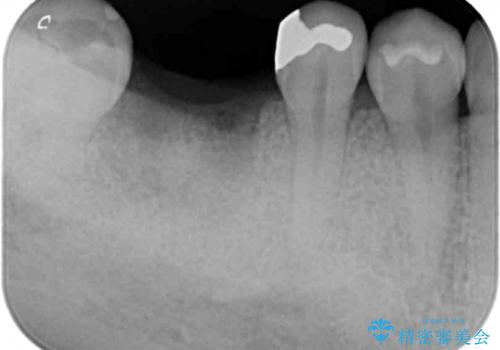

抜歯後は、前後の歯を削らずにしっかりと咬合力を回復できるインプラント治療を選択されました。

虫歯の放置により吸収してしまった骨も造成を行うことでインプラント周囲環境をしっかりと整えています。